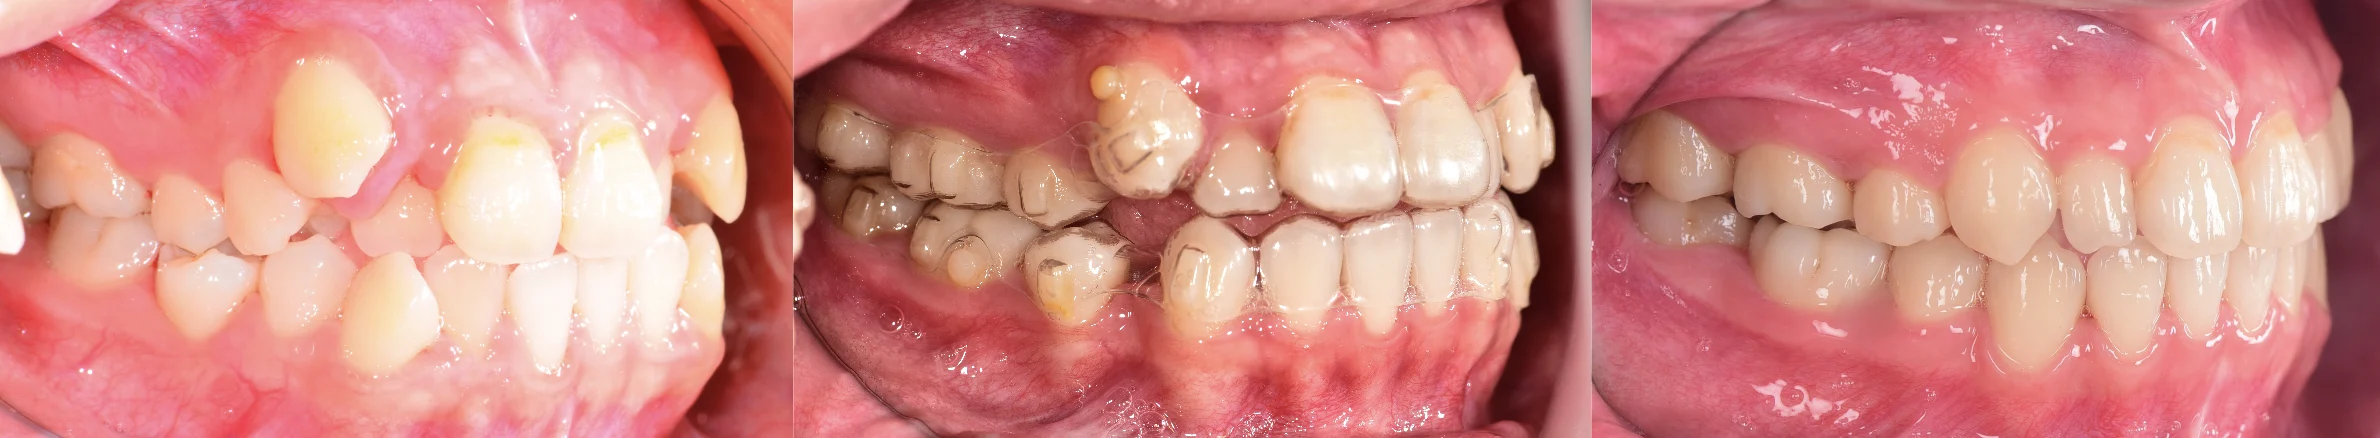

拔牙矯正案例-虎牙